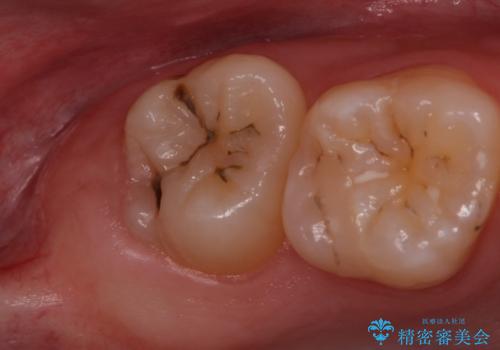

歯の高さ十分がないと十分なブラッシングができなかったり、被せ物をする際に不利になってしまいます。

そのような時は周りの歯茎を除去することで歯の高さを出すことができる場合があります。

今回は親知らずの抜歯と同時に周りの歯茎の除去を行いました。